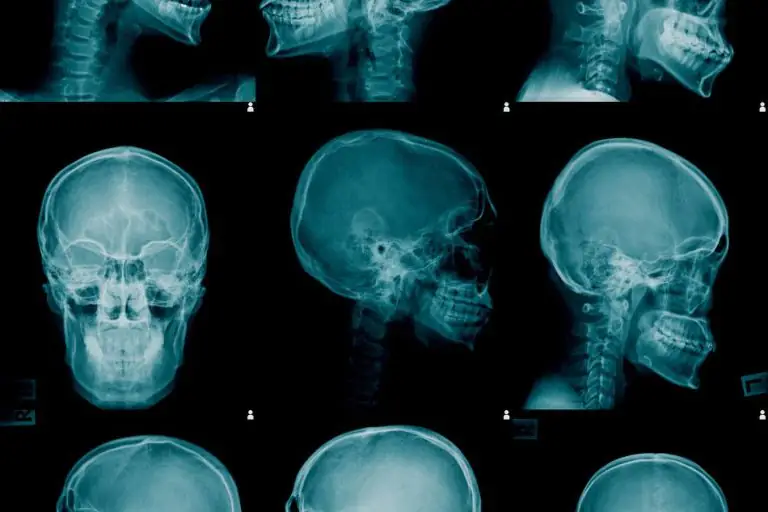

L’esame radiografico del cranio o teleradiografia del cranio consiste in un esame intero-posteriore, postero-anteriore, sub-mento verte, latero-laterale del cranio. Questo esame può essere effettuato anche in formato ridotto, particolarmente indicato per esami pediatrici.